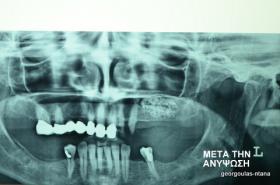

ΑΝΟΙΚΤΗ ΑΝΥΨΩΣΗ ΙΓΜΟΡΕΙΟΥ Κ ΤΟΠΟΘΕΤΗΣΗ 3 ΕΜΦΥΤΕΥΜΑΤΩΝ

Στην ασθενή αυτή πραγματοποιήθηκε ανοικτή ανύψωση ιγμορείου άνω αριστερά. Σε πρώτη φάση πραγματοποιήθηκε η οστική αύξηση και 6 μήνες μετά τοποθετήθηκαν 3 εμφυτεύματα. Τόσο στην πανοραμική όσο και στην τομογραφία κωνικής δέσμης (CBCT) που πραγματοποιήθηκαν 6 μήνες μετά την ανύψωση είναι εμφανής ο σχηματισμός οστού. Η τελευταία ακτινογραφία και φωτογραφία λήφθηκαν 5 χρόνια μετά την προσθετική αποκατάσταση.